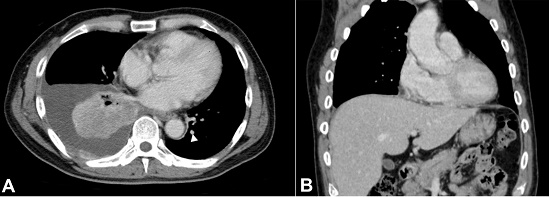

A 58-year-old male presented with cough and dyspnea for several months. He had no significant past medical history other than being a long-time smoker 31 packs/year. He was suspected of heart failure at a previous hospital because of pleural effusion in the chest radiography. He was referred to our hospital and a pleurocentesis was performed, with cytologic studies demonstrating atypical cells with hyperchromatic nuclei, prominent nucleoli and abundant eosinophilic and granular cytoplasm consistent with adenocarcinoma. The carcinoembryonic antigen (CEA) level was of 2260 ng/ml (reference value [RV]: <5.0 ng/ml); however, the alpha-fetoprotein (AFP) was not evaluated. A chest computed tomography (CT) revealed a 6.0-cm long poorly-defined right lower pulmonary lobe tumor with surrounding atelectasis and ipsilateral pleural effusion and a small contralateral pulmonary metastasis (Figure 1A). Whole-body CT scan and bone scintigraphy revealed metastases involving the bones, pleura, left lung (Figure 1A), and brain. At this time, no tumor in the liver was detected and the liver was not cirrhotic (Figure 1B).